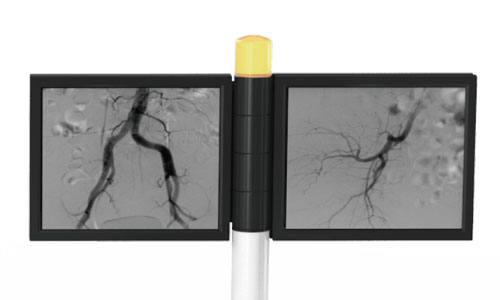

• DSA: DSA is used to clearly visualize blood vessels in a

bony or dense soft tissue environment. Images are produced using contrast medium by subtracting a “pre-contrast image” or mask image from subsequent images, once the contrast medium has been introduced into a structure.

High-quality image chains Ultra-clear images:

• 12-inch dynamic FPD: Large dynamic FPD with smaller pixel size, ensuring distortionless imaging; Wider FOV, avoiding overlapping and omissions, reducing exposure time and radiation dose, and shortening the operation time.